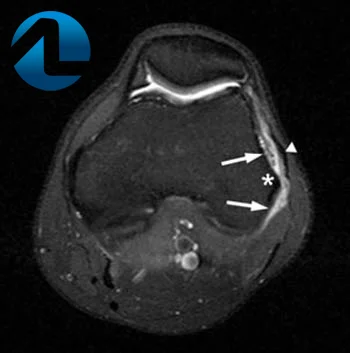

As radiografias simples geralmente não são necessárias para ajudar no diagnóstico, mas a ressonância magnética pode ser usada para mostrar inflamação ao redor e abaixo da banda iliotibial e também excluir outras causas de dor no joelho externo, como lesão na cartilagem, ruptura do menisco lateral, lesão ao ligamento colateral lateral, inflamação do tendão patelar, etc.